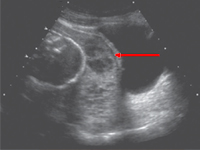

InternaŁożysko przyrośnięte (placenta accreta) jest efektem patologicznej implantacji trofoblastu w głąb doczesnej. Jest to stan rzadko występujący w położnictwie, nie mniej jednak bardzo groźny dla zdrowia i życia rodzącej. Czynnikami ryzyka wystąpienia łożyska wrośniętego są: uprzednio przeprowadzone operacje macicy, łożysko przodujące, wiek matki powyżej 35 lat, uszkodzenie endometrium, mięśniaki podśluzówkowe. Patogeneza jest nieznana, a postępowanie diagnostyczne i lecznicze pozostaje istotnym problemem klinicznym.